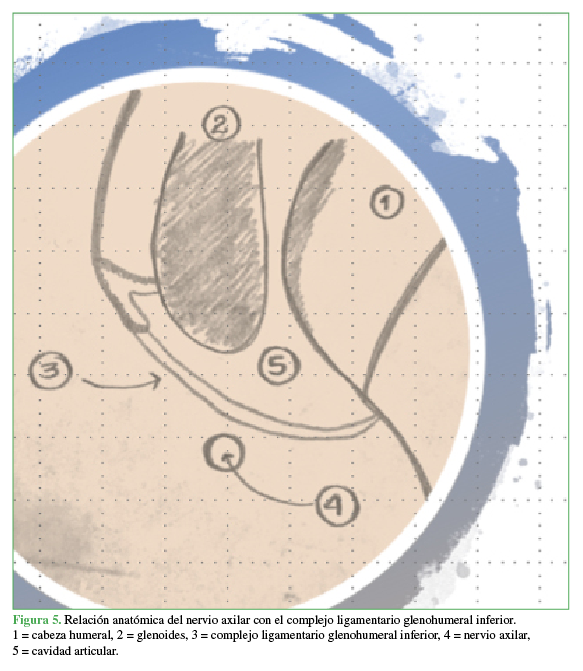

11. Maman E, Morag G, Safir O, Benifla M, Mozes G, Boynton E. The anterior trunk of the axillary nerve: surgical anatomy and guidelines. A fresh, cadavers study. J Orthopaedics 2008;5(2):e7. http://www.jortho.org/2008/5/2/e7

12. Price MR, Tillett ED, Acland RD, Nettleton GS. Determining the relationship of the axillary nerve to the shoulder joint capsule from an arthroscopic perspective. J Bone Joint Surg Am 2004;86(10):2135-42. PMID: 15466721